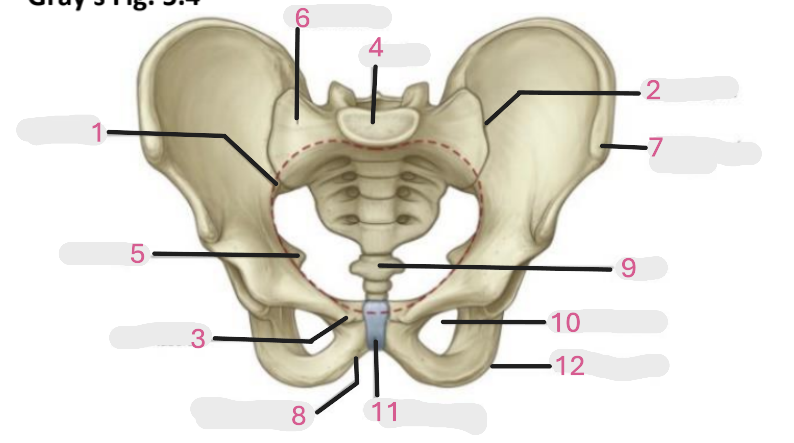

Where is the pelvic inlet

1

Where is the sacro-iliac joint

2

Where is the pubic tubercle

3

Where are the S1 body

4

Where is the ischial spine

5

Where is the ala of sacrum

6

Where is the anterior superior iliac spine

7

Where is the ischiopubic ramus

8

Where is the coccyx

9

Where is the obturator foramen

10

Where is the pubic symphysis

11

Where is the ischial tuberosity

12